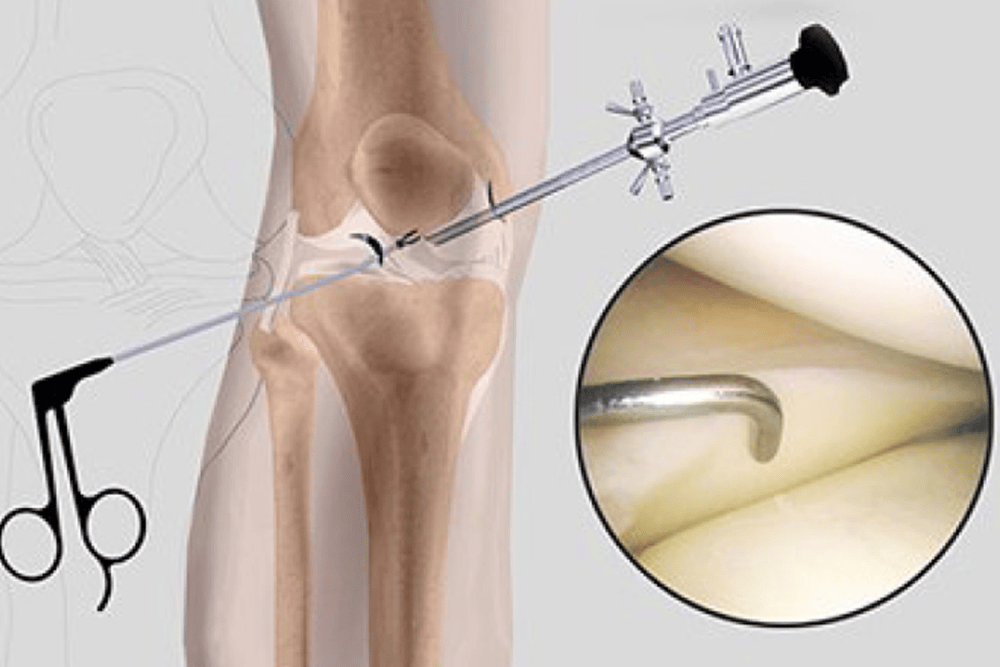

Arthroscopy is a minimally invasive surgical procedure that allows surgeons to diagnose and treat knee joint problems using a small camera and specialized instruments inserted through tiny incisions. This approach minimizes tissue damage and promotes faster healing compared to traditional open surgery.